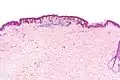

تكبير منخفض